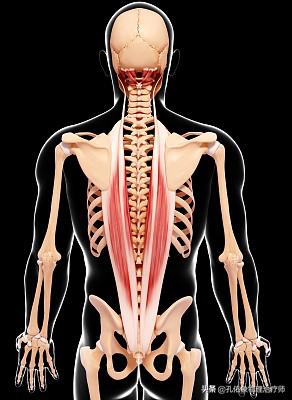

第二に、硬いベッドで寝ている期間、急性期には運動する必要がないが、慢性期には硬いベッドで寝ているだけで、一定の姿勢を維持するために対応する運動が不足している場合、長期的には背中の傍脊柱筋を作ることになります。の状態の適応的短縮この状態の主な特徴のひとつは、短縮した組織構造が、身体をより楽な姿勢に変えるのを妨げていることである。もちろん、私たちの身体は望ましい姿勢を完成させるための代償動作を見つけるのがとても上手なので、患者は通常このことに気づかない。短縮した組織は身体の局所的なアンバランスを引き起こし、時間が経つにつれて、硬いベッドで寝ることがますます苦痛になっていく。